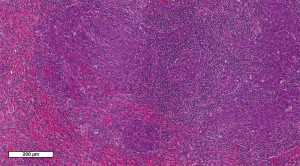

A 40-year-old male with a significant history of smoking presented to the clinic with an enlarged cervical lymph node. The initial clinical impression was lymphadenitis, for which appropriate treatment was administered. However, the patient showed no clinical improvement following therapy. Consequently, an ultrasound examination was performed, revealing multiple enlarged cervical lymph nodes. A true-cut biopsy revealed metastatic poorly differentiated carcinoma. Comprehensive imaging studies, including computed tomography (CT) scans of the head, neck, chest, abdomen, and pelvis, as well as magnetic resonance imaging (MRI) of the head and neck and a single-photon emission computed tomography/positron emission tomography (SPECT/PET) scan, were performed. Together with the physical examination and laboratory findings, the patient was diagnosed with NPC, staged as T3N2M0. Serology for Epstein Barr virus was performed, which was found to be positive. Based on these findings, and following multidisciplinary discussion in the Head and Neck Tumor Board, the patient was planned for concurrent chemoradiotherapy consisting of weekly cisplatin and radiotherapy (70 Gy in 33 fractions). During the course of treatment, the patient developed severe mucositis, significantly impairing oral intake, necessitating the placement of a percutaneous endoscopic gastrostomy (PEG) tube for nutritional support. Post-treatment whole-body MRI and PET/CT imaging demonstrated regression of the primary disease with residual uptake in the retropharyngeal lymph nodes, along with new osseous lesions involving the right iliac bone, right femoral head, and pubic bone. A bone biopsy from the right pelvic bone confirmed metastatic involvement. The patient was subsequently started on systemic chemotherapy with weekly paclitaxel/carboplatin and capecitabine. Following six cycles of chemotherapy, repeat PET/CT imaging showed persistent bone metastases and stable mild uptake in the left nasopharyngeal region. Given the extent of bony disease, SBRT was not pursued, and systemic therapy was switched to gemcitabine. Subsequent PET/CT imaging revealed disease progression with new involvement of abdominal lymph nodes. As a third-line approach, the patient was initiated on pembrolizumab, administered every three weeks for a total of (38 cycles) and received stereotactic body radiotherapy (SBRT) to retroperitoneal abdominal metastases (5 fractions). During the course of treatment, the patient developed additional metastatic sites, including a paraspinal mass and axillary lymphadenopathy, for which local radiotherapy was administered. On surveillance follow-up, the patient reported intermittent left-sided abdominal pain. Further evaluation with PET/CT of the abdomen and pelvis revealed a splenic lesion, raising concern for disease progression. These findings were confirmed with MRI of abdomen. A tumor board was formed in the hospital where the team discussed the case thoroughly to make a final diagnosis and a decision. The board agreed to perform splenectomy for diagnostic and therapeutic purposes. There was a mutual agreement between members of the tumor board and the team preferred to have a laparoscopic splenectomy for diagnostic and therapeutic purposes rather than an open laparotomy. Patient was given pneumococcal, meningococcal, and Haemophilus influenzae vaccines prior to the procedure. Patient underwent laparoscopic splenectomy and distal pancreatectomy with no complications. After performing the procedure, the specimen was sent for histopathology and a week later, his pathology results came out that confirmed metastasis from NPC as a primary origin. Histopathological examination of the splenic lesion revealed subcapsular replacement of the normal splenic parenchyma by metastatic neoplasm (Figure 1). The neoplastic cells exhibited moderate eosinophilic to amphophilic cytoplasm, round nuclei, and prominent eosinophilic nucleoli, arranged in sheets (Figure 2). Keratinization was absent, and a prominent lymphoplasmacytic infiltrate was noted surrounding the tumor cells (Figure 3). Immunohistochemistry showed strong and diffuse membranous and cytoplasmic positivity for cytokeratin 5/6 (CK5/6) and strong nuclear positivity for P63 in the neoplastic cells (Figures 4,5). In situ hybridization for Epstein-Barr virus (EBV-ISH) demonstrated strong and diffuse nuclear positivity, confirming EBV association (Figure 6). The patient was kept under observation for several months. Follow-up imaging subsequently revealed new metabolic activity in the stomach. A biopsy of the gastric lesion confirmed metastatic disease. As a result, systemic therapy with carboplatin in combination with pembrolizumab was reinitiated. Due poor general status of the patient and advanced unresponsive disease the treating team kept him on palliative treatment of chemotherapy and radiotherapy. All procedures performed in this study were in accordance with the ethical standards of the institutional and/or national research committee(s) and with the Declaration of Helsinki and its subsequent amendments. Written informed consent was obtained from the patient for the publication of this case report and accompanying images. A copy of the written consent is available for review by the editorial office of this journal.